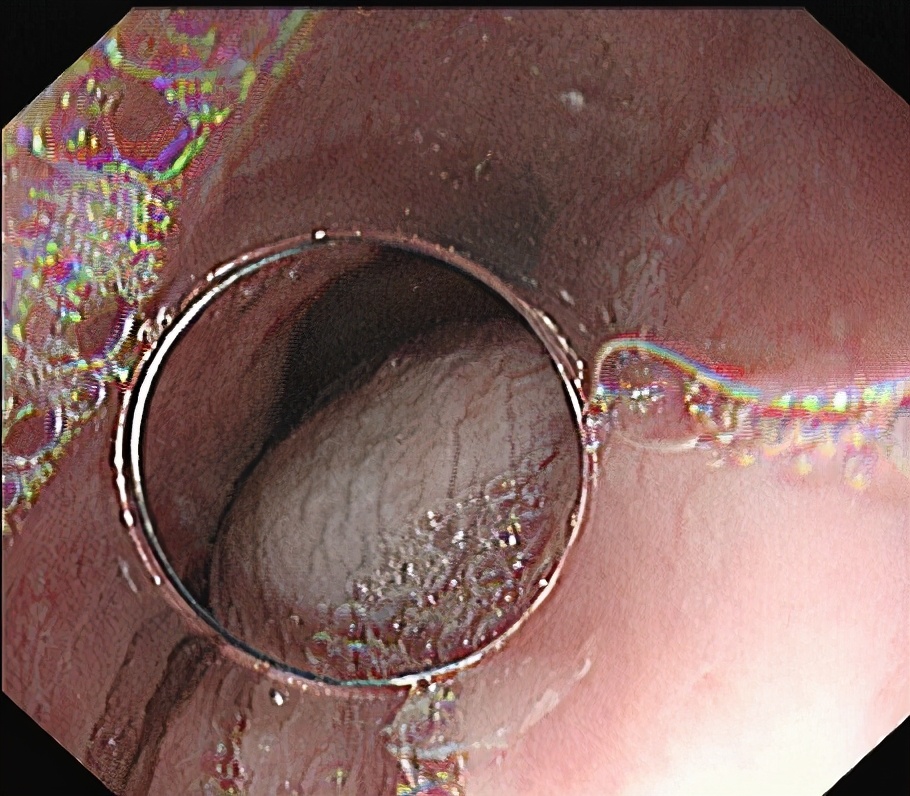

常规插入内镜,黏膜下注射。

02

食管粘膜层切开。